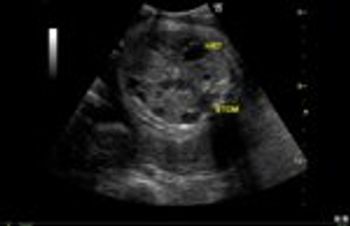

This woman presented with pelvic pain and discomfort. What is your diagnosis?